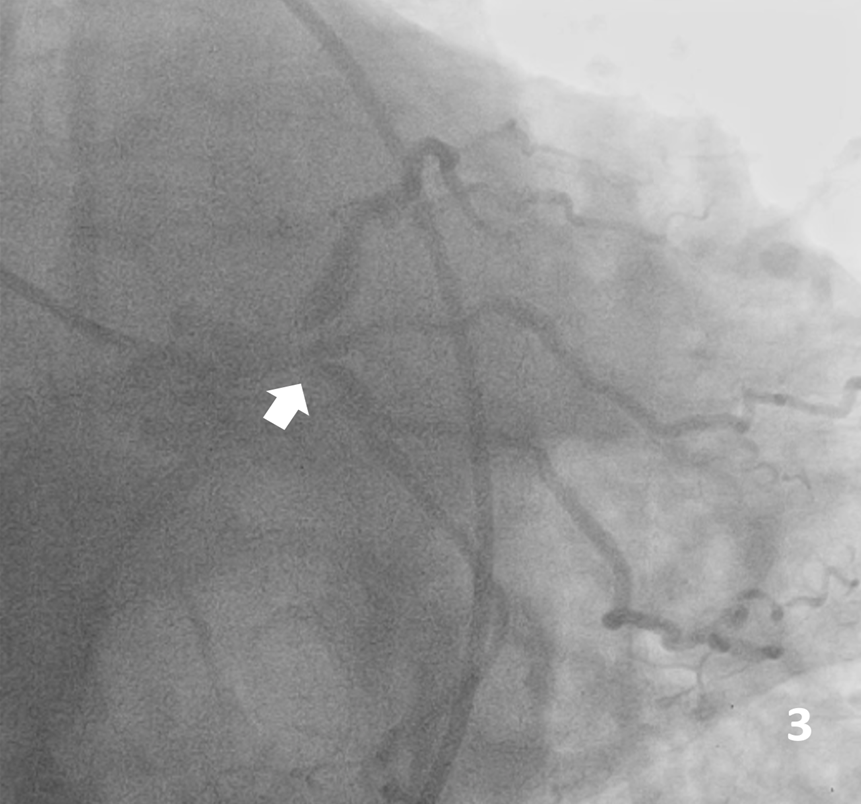

A 66-year-old male Jehovah’s Witness arrived at the emergency room having experienced typical persistent angina. Upon arrival, he was hemodynamically unstable. Electrocardiogram showed a high-risk pattern (Figure 1) and hs-cTn of 21 000 ng/L. Coronary angiography showed critical left distal main disease with trifurcation lesion to the left anterior descending artery (LAD), ramus intermedius, and left circumflex artery (LCx) (medina 1-1-1-1), and an 80% lesion in the middle segment of the LAD (Figure 2, 3). After medical consensus with surgeons, we decided to proceed with percutaneous coronary intervention.